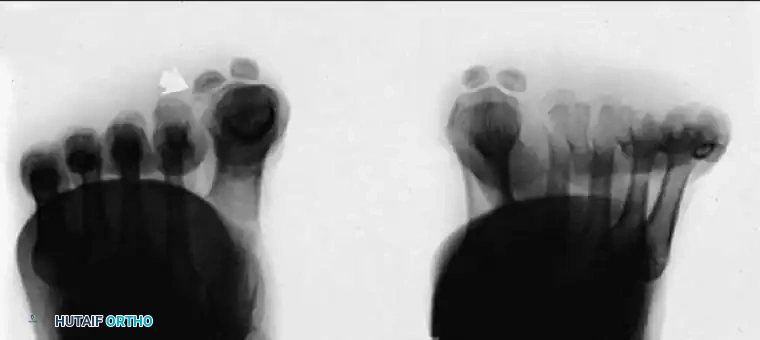

Fig. 78-97 Hallux valgus (A), and on axial sesamoid view (B), degenerative changes present with subluxation of the sesamoids.

Fig. 78-98 Techniques for obtaining axial sesamoid views. A and B, View may be taken with the patient up on toes (A) or standing on an inclined plane (B). C and D, Axial sesamoid view taken from the front while the patient stands on an inclined plane.